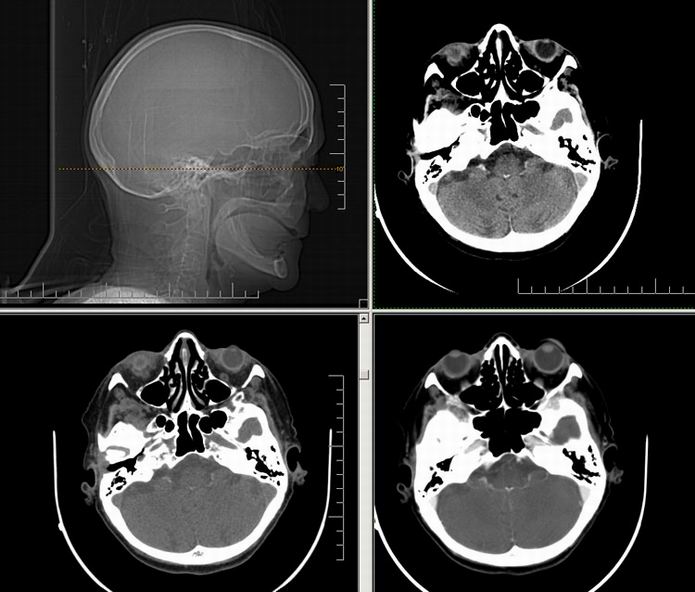

Est ce que qqun a des coupes axiales de crâne pour m'aider à réviser mon anatomie. Merci

Pour compléter tes révisions, Poupette vient de nous faire parvenir ces planches bien utiles: Planches de coupes axiales cérébrales, dans la rubrique COURS / ANATOMIE